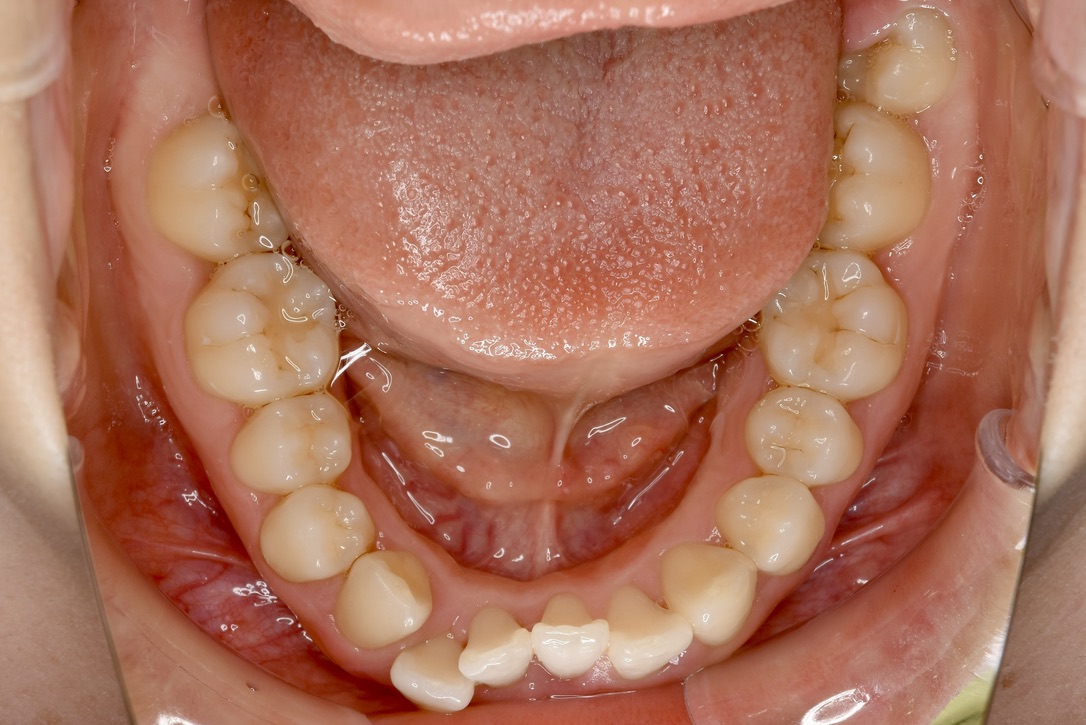

21歳 女性 治療期間:1年1ヶ月

叢生(ガタガタ)

マウスピース矯正装置(インビザライン)

BEFORE

AFTER

診断名・主な症状

叢生

治療内容

上下とも歯並びの横幅を広げながら、でこぼこを解消しました。

マウスピース矯正(インビザライン)

抜歯あり(智歯抜歯)

治療期間

1年1ヶ月